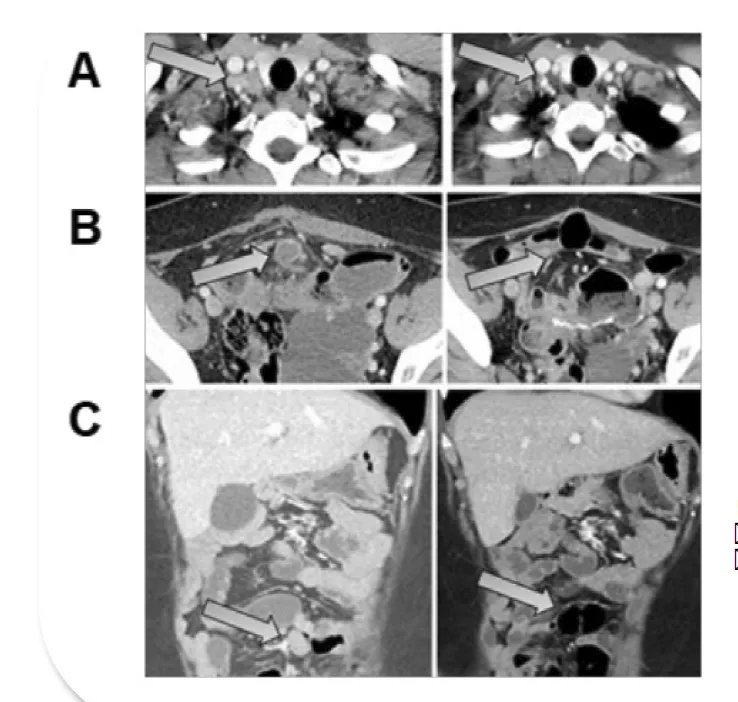

2025年美国临床肿瘤学会(ASCO)大会上,这款疗法公布了突破性数据:在针对中国人群的探索性临床试验(NCT06526832)中,初步结果显示:疾病控制率(DCR)100%(2/2),客观缓解率(ORR)50%(1/2);最佳反应患者的多个病灶持续显著缩小,其中肝脏靶病灶在输注后84天缩小57.1%,门静脉癌栓缩小51.8%。

▲截图源自“ASCO”